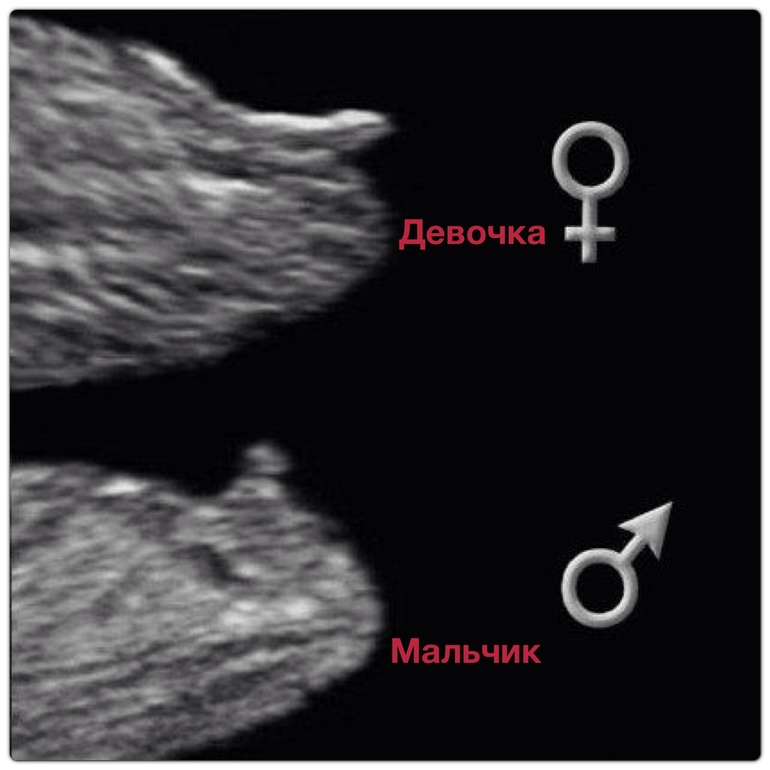

Вот смотрите я подписала, где ваша писюлька она идет прямо в доль позвоночника. И на втором фото это чем отличаются бугорки на 12 неделях.

20.01.2014

Спасибо))) будем ждать))) дальнейшего развития событий, все такие знающие))) где вы все это берете, я не имею ввиду ваш опыт))) я имею ввиду картинки такие

В гугле мульен картинок

Ну вот смотрите мои девченки 3-4

21.01.2014

Ого, какие фото!!!!!!!! Если так, то у нас отчётливый сыночек

Покажите вашу фотку